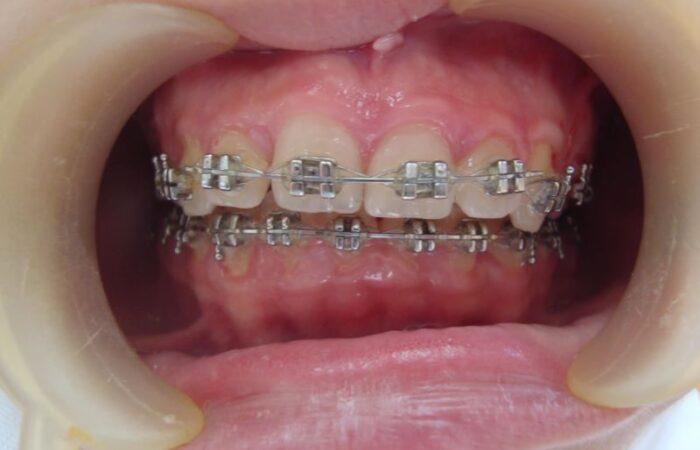

المعالجة التقويمية للأسنان – الاختلاطات ودور الأخصائي للحدّ منها

الجراحة التقويمية للفكين – الاستطباب، الأنواع وما اختلاطاتها؟

أجهزة تقويم الأسنان الوظيفية – أنواعها، آلية عملها ومدة العلاج

تقويم الأسنان الشفاف – الاستطبابات، الميزات والعيوب

تقويم الأسنان – خطة المعالجة، التقويم الثابت وآلية عمله

تقويم الأسنان – التشخيص والاستطباب